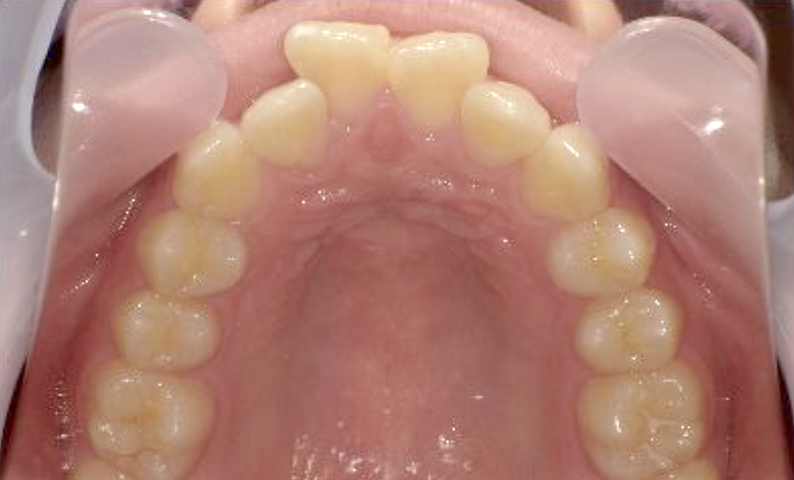

症例_001 上下顎の部分矯正

治療期間:12ヶ月金額:54万円+税女性前歯のガタガタ逆八の字

| Before | After |